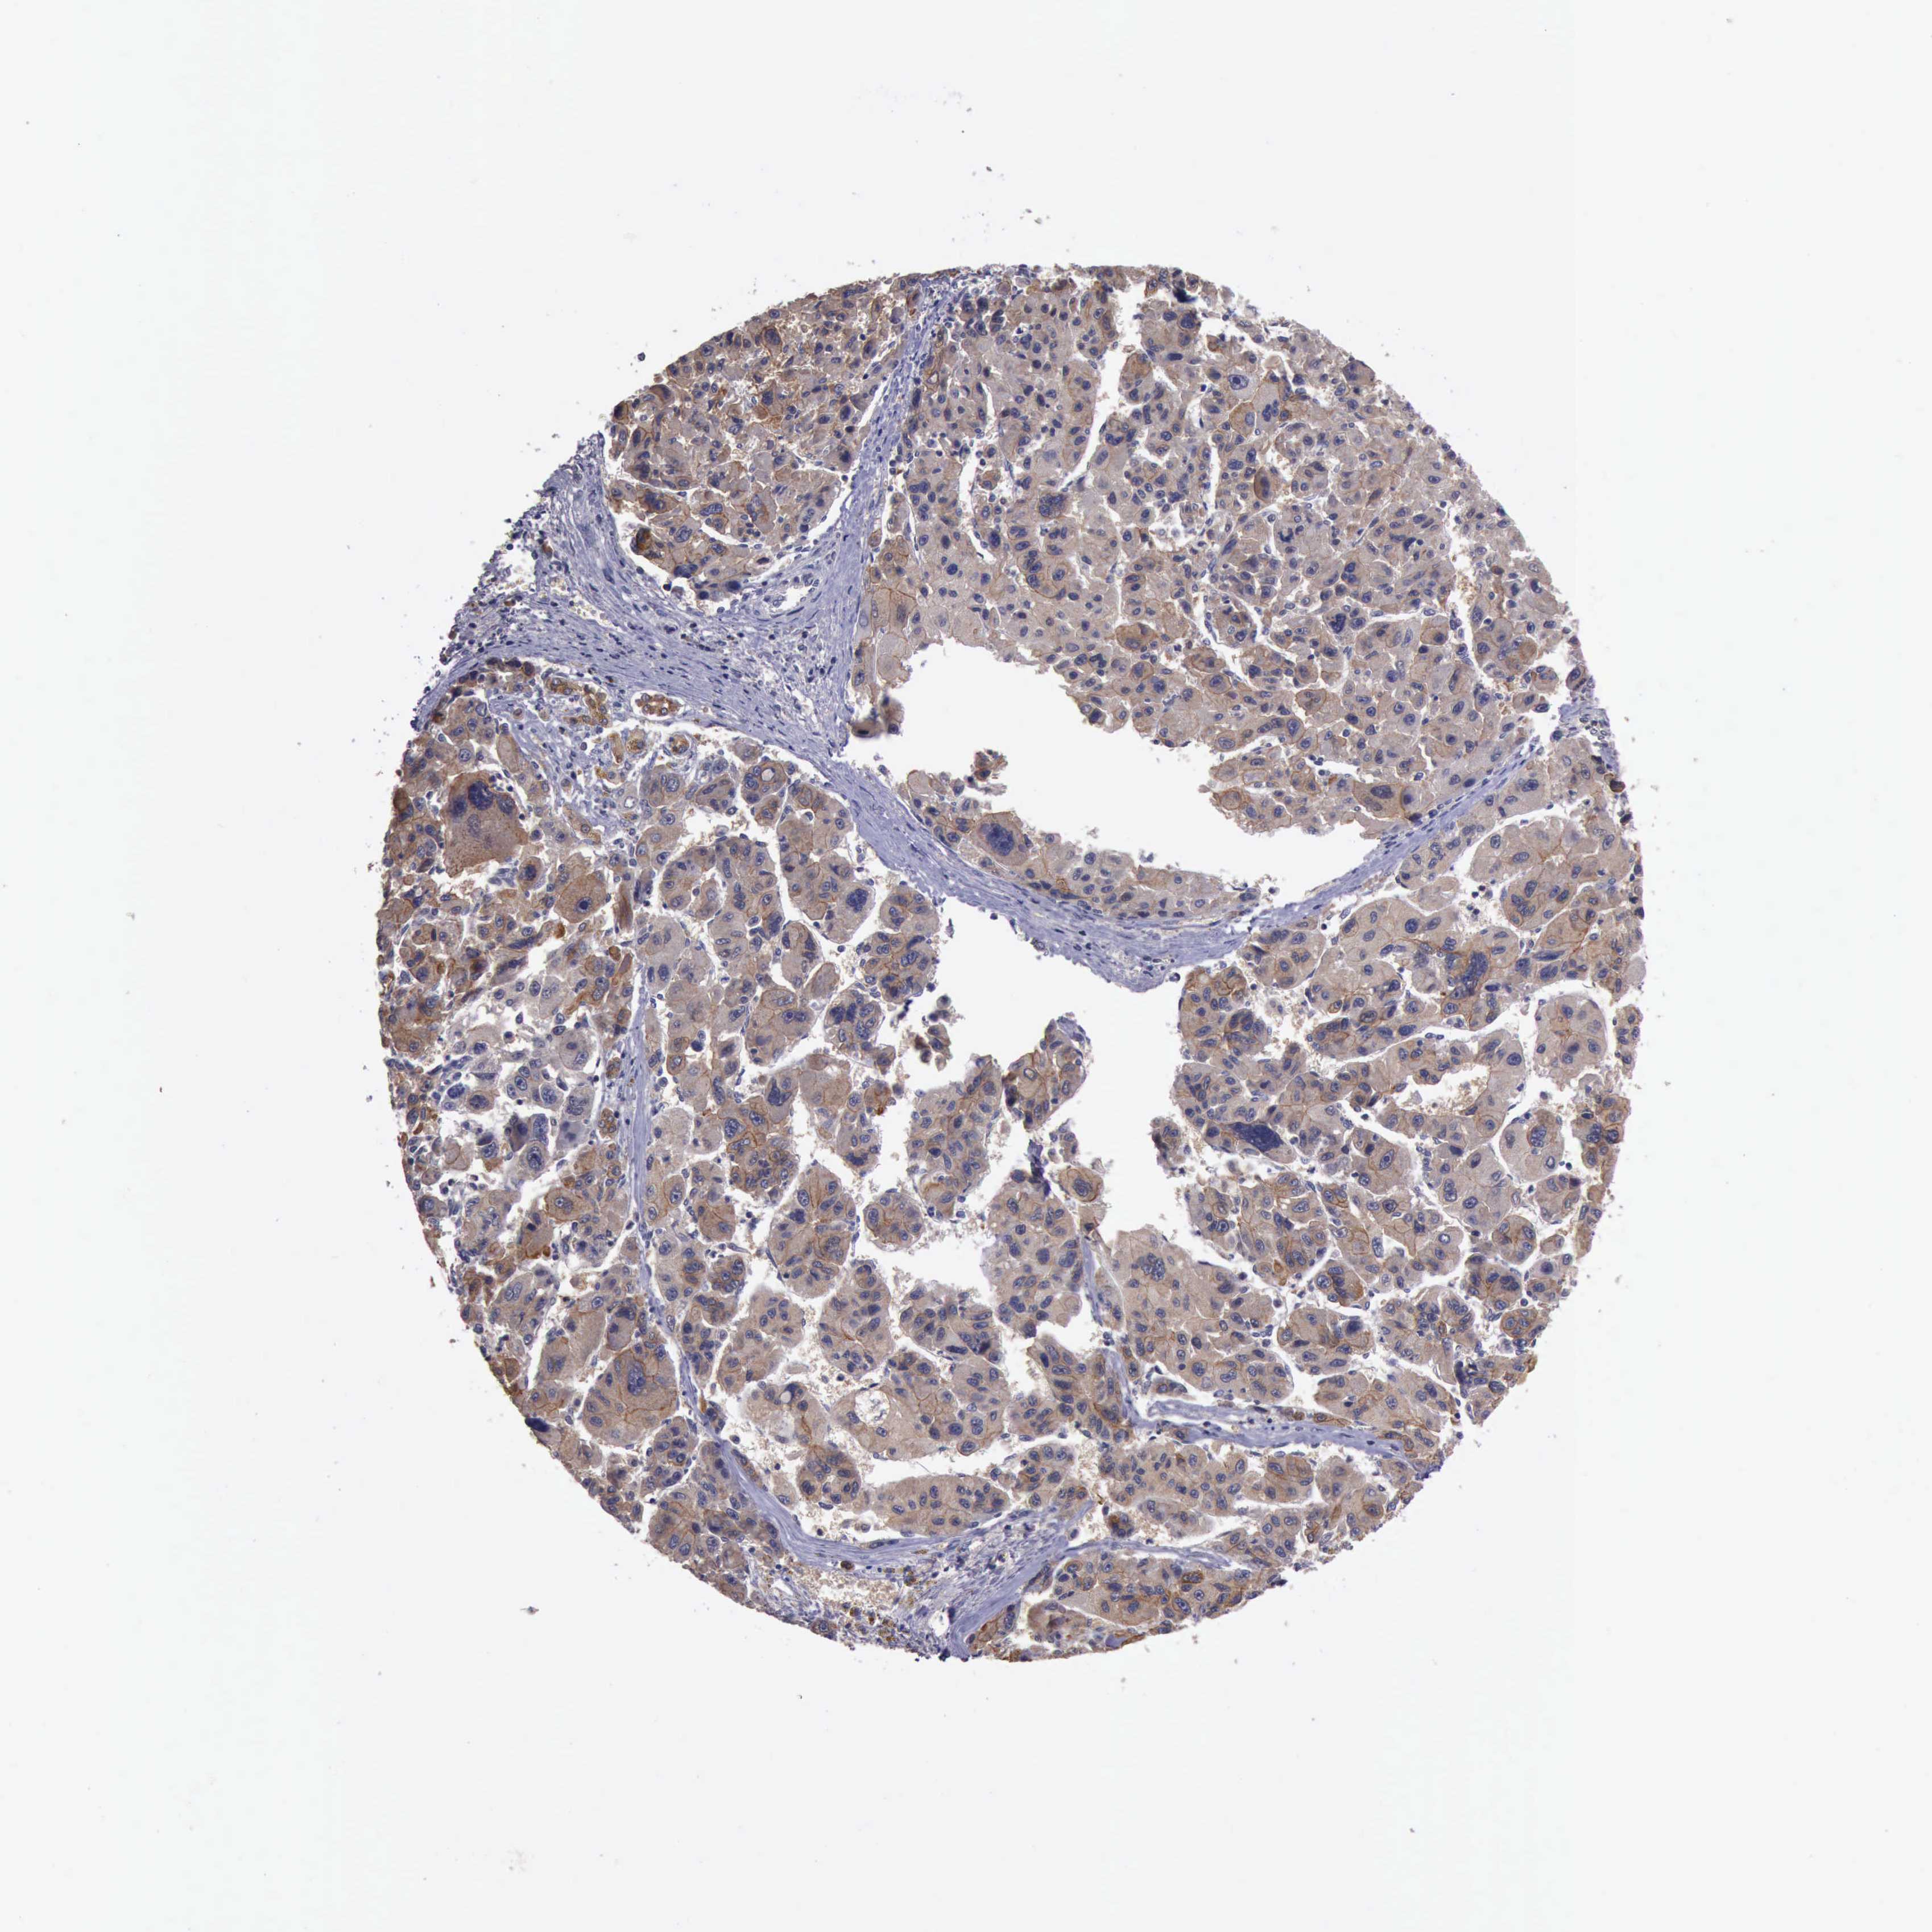

LIVER CANCER - Protein expressioni

A mouse-over function shows sample information and annotation data. Click on an image to view it in a full screen mode. Samples can be filtered based on level of antibody staining by selecting one or several of the following categories: high, medium, low and not detected. The assay and annotation is described here.

Antibody stainingi

Antibody staining in the annotated cell types in the current human tissue is reported as not detected, low, medium, or high, based on conventional immunohistochemistry profiling in selected tissues. This score is based on the combination of the staining intensity and fraction of stained cells.

Each image is clickable and will lead to virtual microscopy that enables deeper exploration of all samples and also displays staining intensity scores, fraction scores and subcellular localization as well as patient and tissue information for each sample.

Antibody HPA001114

Antibody HPA042505

Staining

High

Medium

Low

Not detected

Intensity

Strong

Moderate

Weak

Negative

Quantity

>75%

75%-25%

<25%

None

Location

Nuclear

Cytoplasmic/membranous

Cytoplasmic/membranous,nuclear

Carcinoma, Hepatocellular, NOS

Cholangiocarcinoma